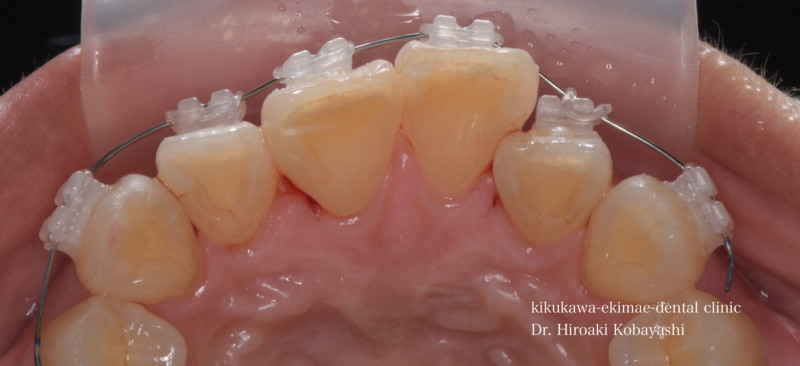

歯並びを気にされて来院されました。見た目改善を目的にワイヤーによる部分矯正を希望されました。 ブラケット装着用のマウスピースを作り、ブラケット装着を行います。   弱い力をかけながら、ワイヤーにより歯を動かします。強い力を急にかけると歯の根が吸収されてしまいます。なので弱い力で歯を動かすことによって根への負担が少なく歯根吸収のリスクが少なくなります。               6ヶ月程度で歯の並びを改善することができました。   before after